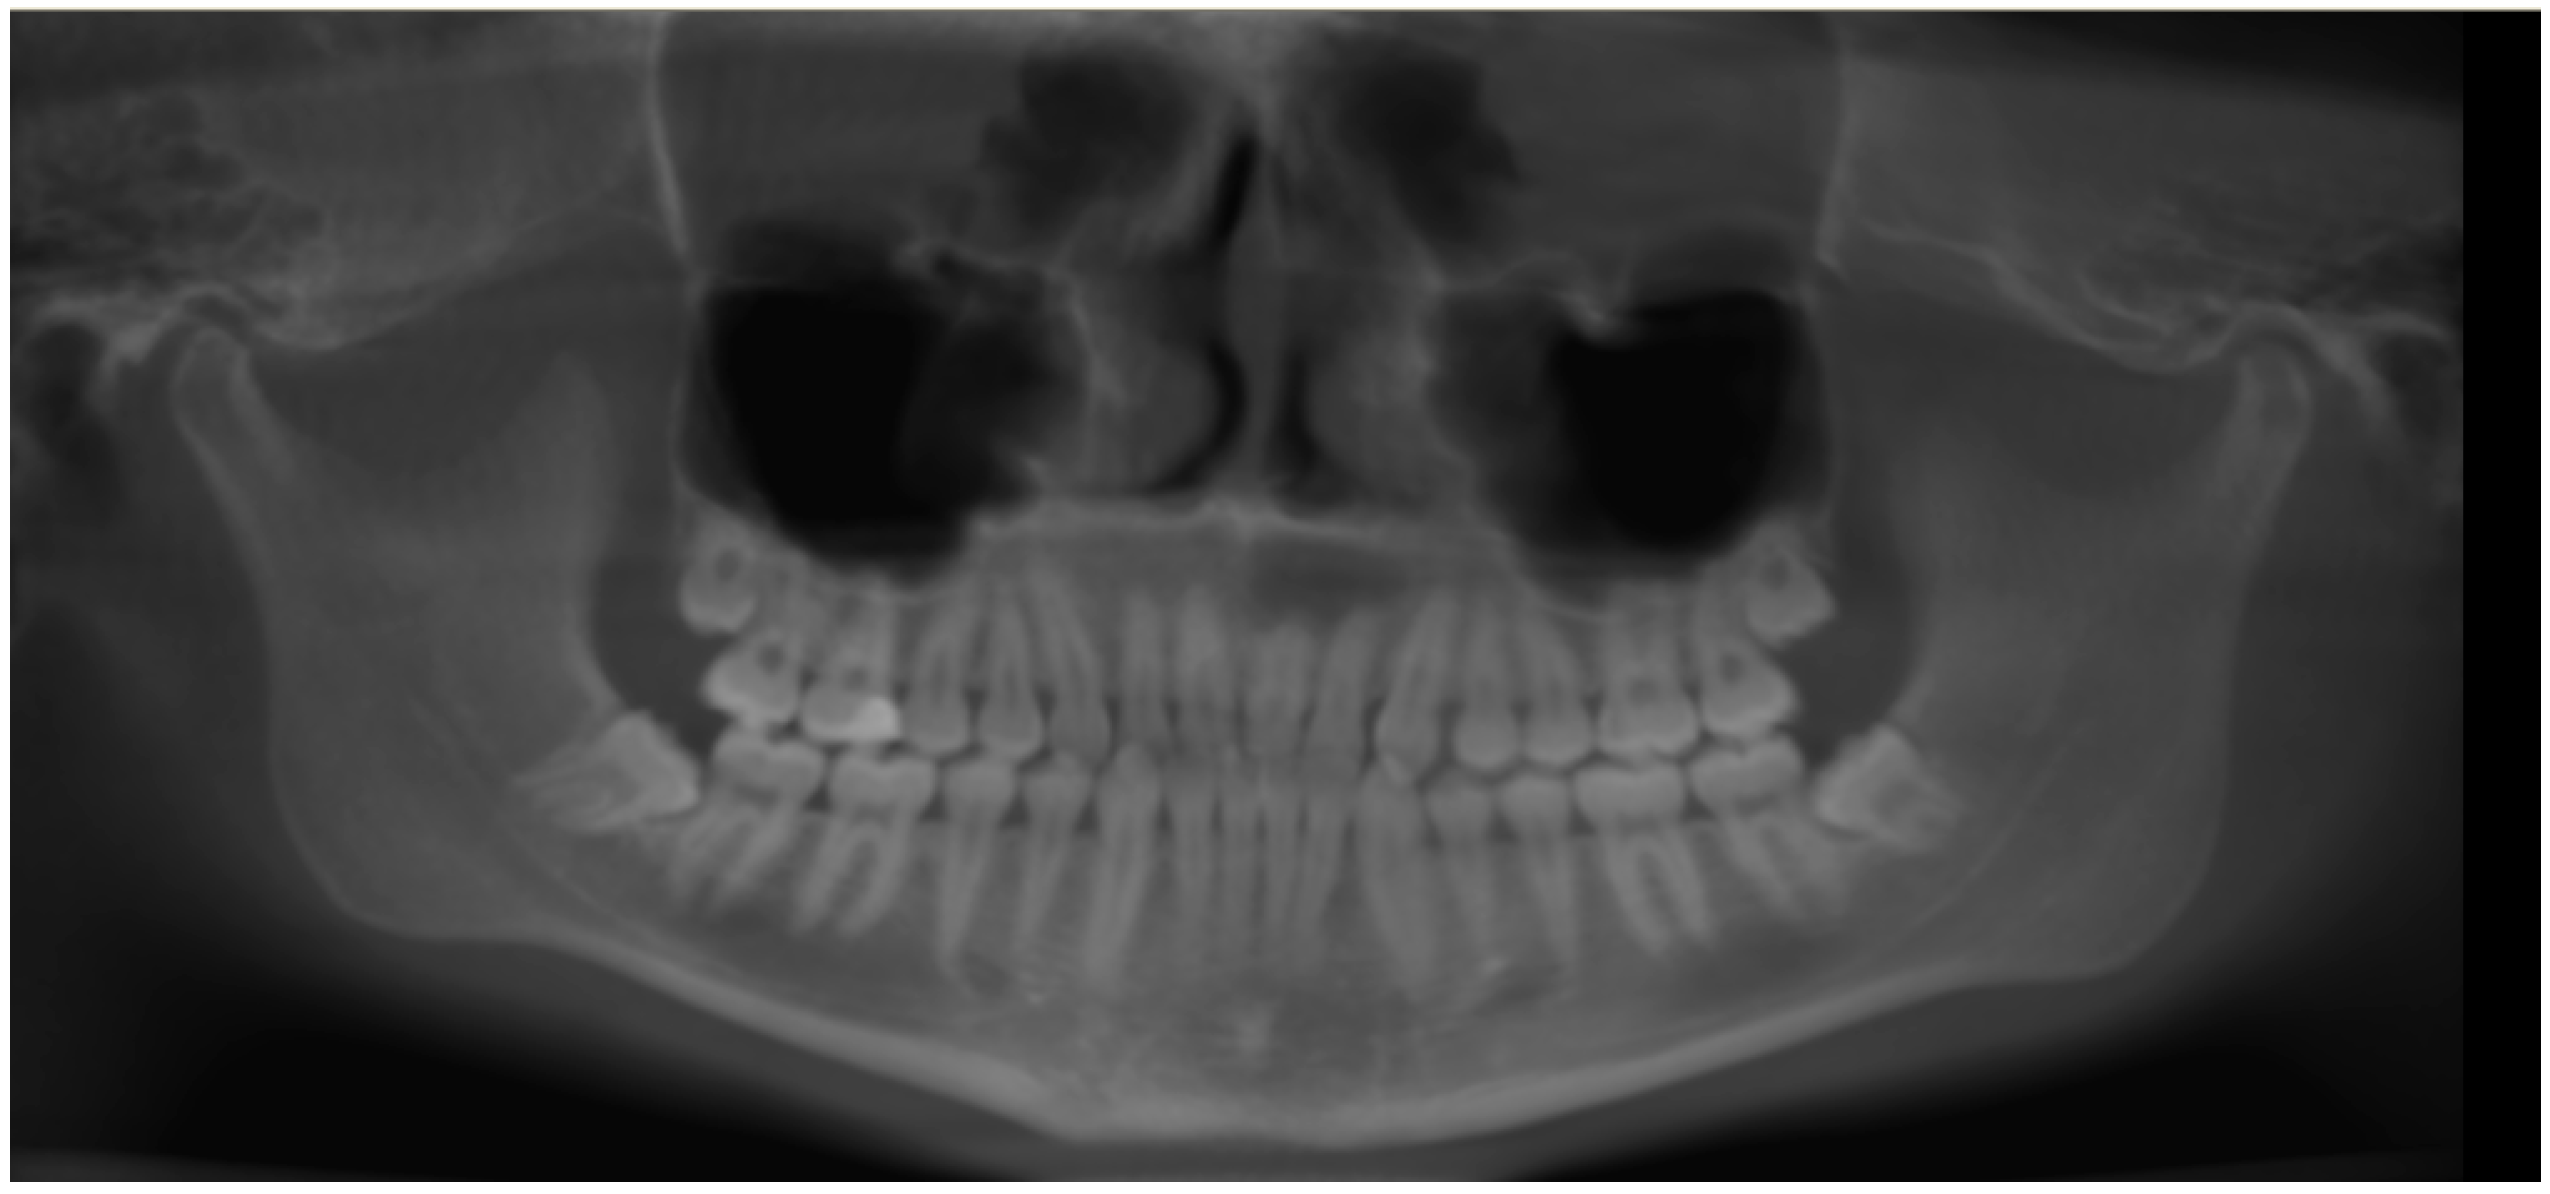

Initially, a panoramic image of patients was used for a general dental evaluation and select cases according to inclusion criteria as shown in Figure 2. An axial view of the maxillary arch was used to evaluate the number of roots and canals in maxillary molars as shown in Figure 3. Subsequently, the coronal view was used to evaluate the type of Vertucci’s classification in the palatal root of maxillary first molar as shown in Figure 4.

Figure 2.

Panoramic view showing intact all permanent first molars.